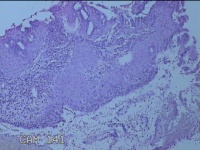

宫颈6点、12点组织

性别

女

年龄

39岁

临床诊断

人乳头瘤病毒感染

一般病史

宫颈筛查异常。

标本名称

大体所见

1.“宫颈6点组织”:灰白粉红色组织0.7x0.5x0.2cm一块。 2.“宫颈12点组织”:灰白暗红色组织 0.8x0.7x0.2cm一块。